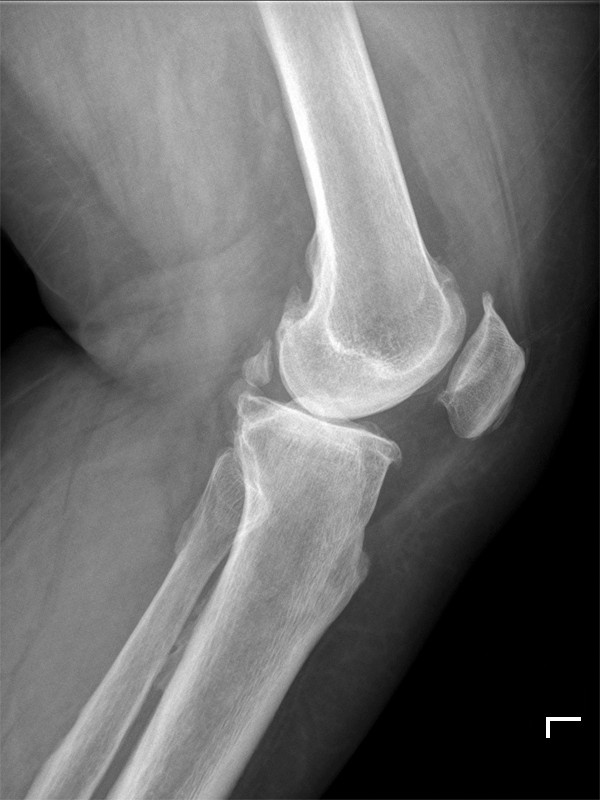

퇴행(degeneration)

- 닫혀진 무릎관절 (Knee joint space)

- 이곳저곳 골극(spur)